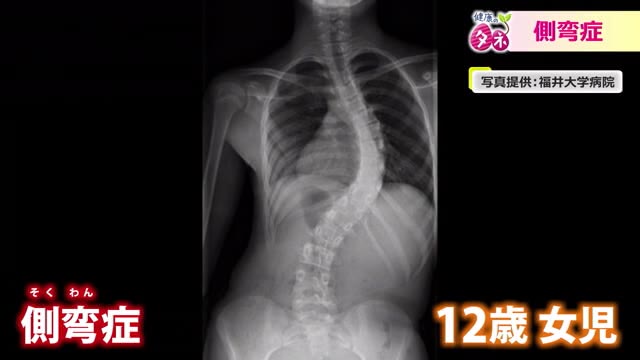

左右に大きく曲がった背骨。「側弯症」の症状が進んだ12歳の女の子のレントゲン写真です。

「側弯症は正式名称は脊柱側弯症と言う。脊柱というのは背骨、側弯は横に曲がるということだが、横だけでなくねじれるように曲がるので、見た目が変形する病気。レントゲンの正面で曲がっているところの角度を測って10度以上あるものを側弯症と定義する。これだけ曲がっていても痛みがほとんどないのが特徴」

「この子の場合は12歳の段階で、角度が60度ある状態。この状態だと大人になっても進行してしまうので手術が必要になった。背骨にねじを入れていき、ねじを棒で連結して変形を矯正して固定する」